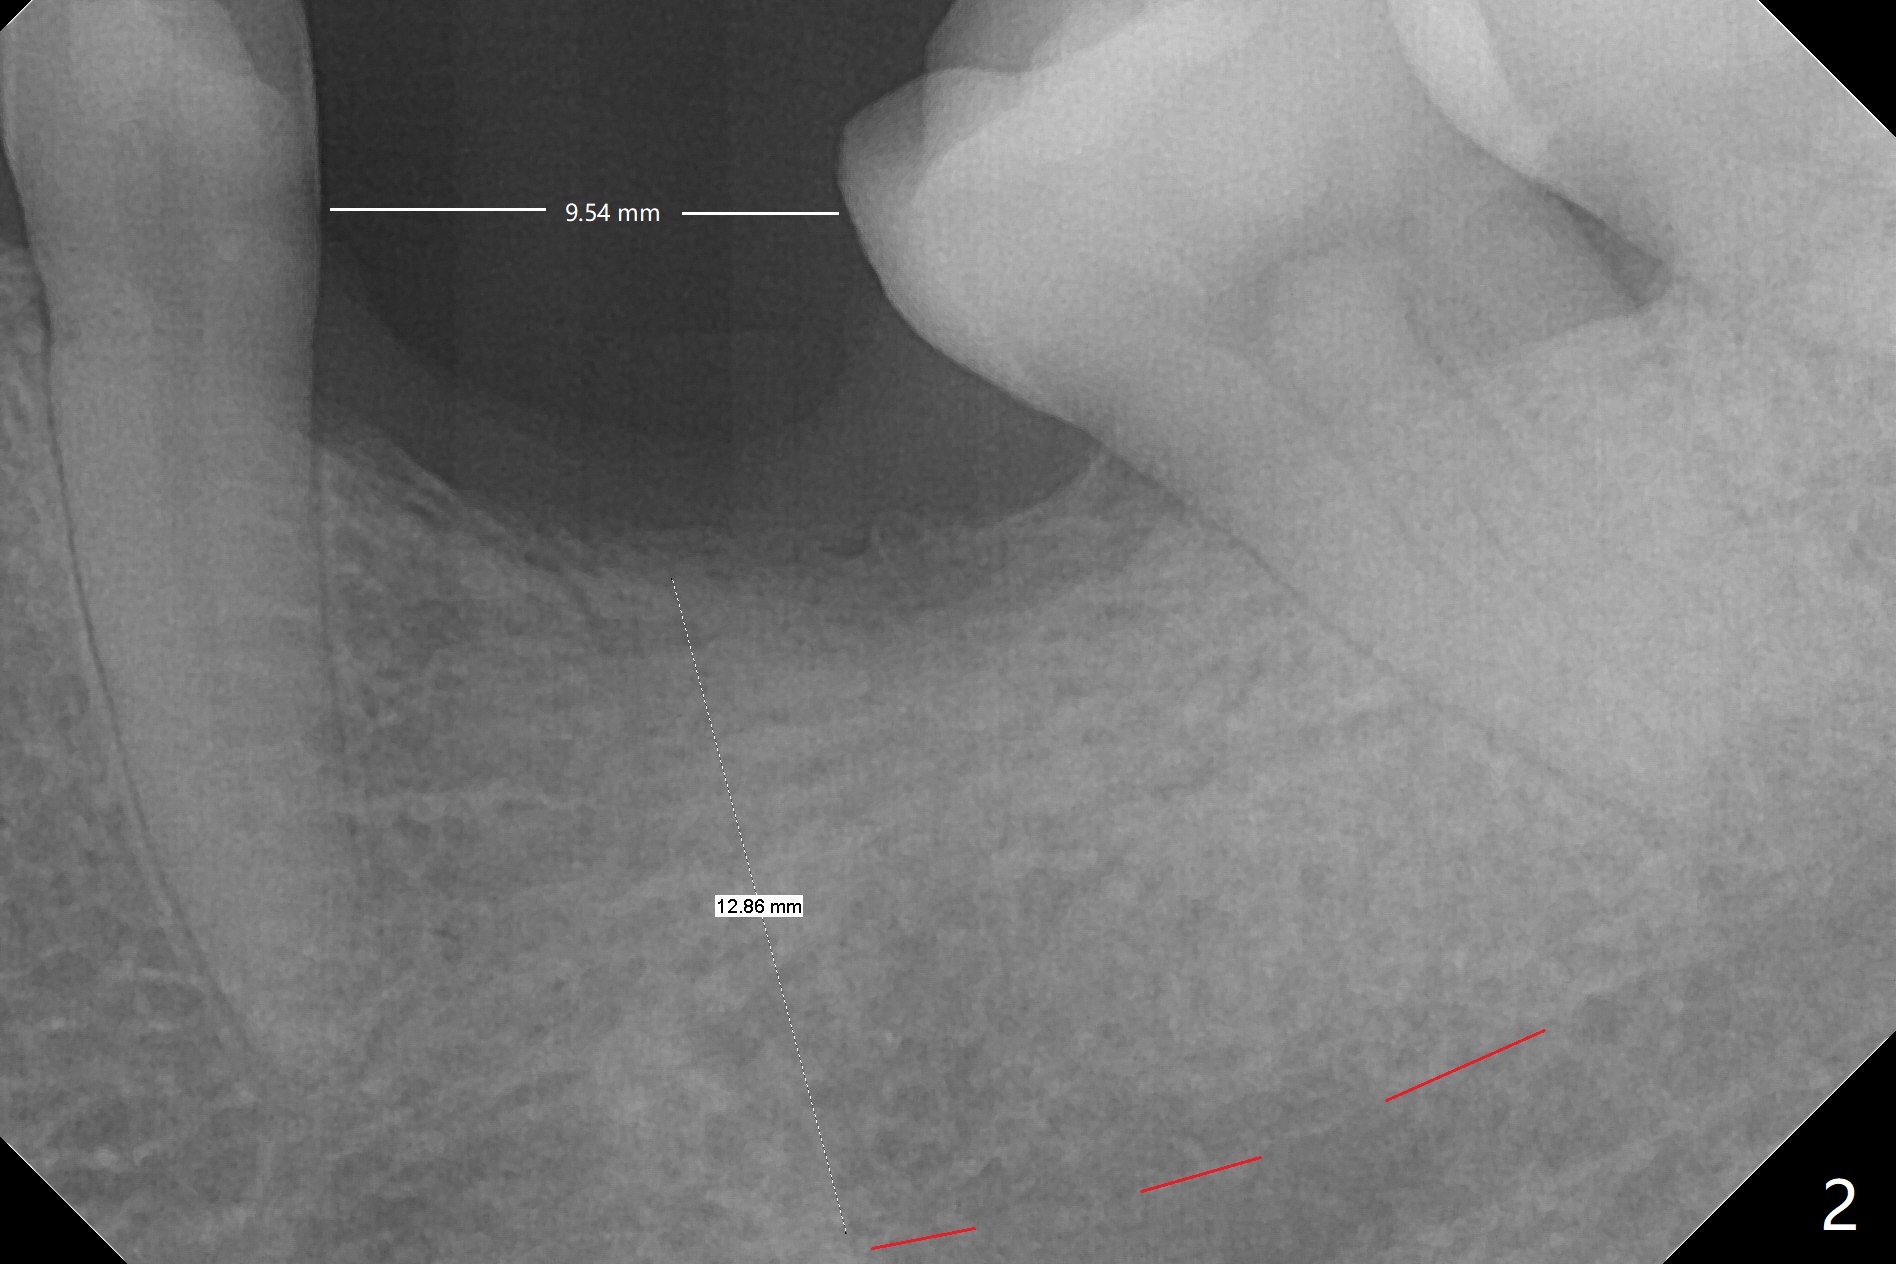

A 46-year-old woman has lost the tooth #19 since middle school with supraeruption of the tooth #14 and mesial tilt of the teeth #17 and 18 (Fig.1 arrows). After slightly distal placement of an implant at #19 with guided surgery (Fig.2), two minimplants will be placed for intrusion of the tooth #14. Upon implant osteointegration, a provisional will be fabricated with supraocclusion to facilitate the intrusion and upright the tooth #18 with extraction of the tooth #17. Fig.3 is a coronal section of CT of the roots of the tooth #14, showing 1.6x8 mm and 1.6x10 mm mini-implants to be placed mesiobuccal and distopalatal. A 5x8.5 mm implant will be placed at the site of #19 (Fig.4).